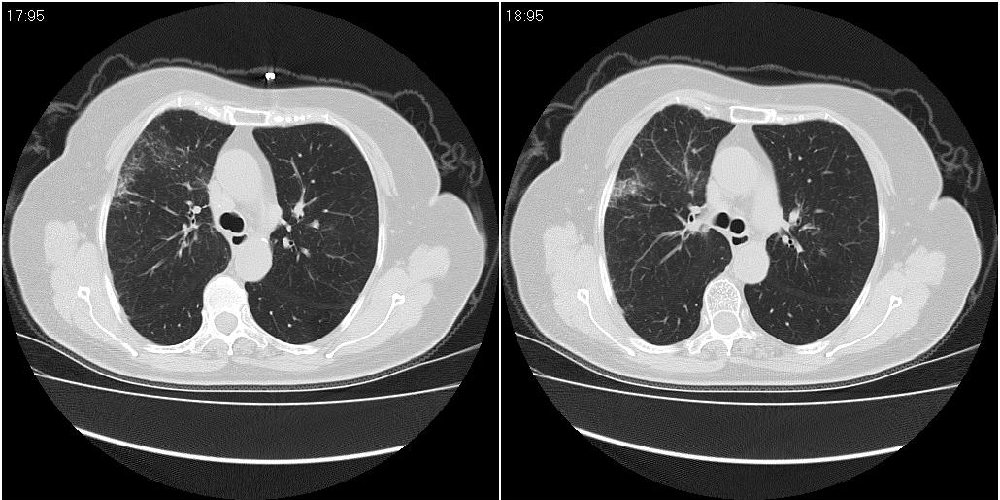

女性,72岁。去年9月份发现肺部病变,诊为肺结核并进行正规治疗至今,但复查后发现ct表现几乎没有变化。

右中间段支气管局限性狭窄,右中叶支气管亦稍显狭窄,但并未见明显占位表现,半年多了,无变化也许是好事,可能为炎性狭窄,建议继续随访。

双肺继发型tb并右中叶内膜tb,轻度支扩,左下胸膜肥厚粘连。

右中间段支气管局限性狭窄,右中叶支气管亦稍显狭窄.

双肺继发性肺结核并右肺中叶节段性肺不张,左下胸膜肥厚粘连。

右肺中叶节段性肺不张,考虑结核或慢性炎症,建议做纤支镜检查。

双肺继发性肺结核并右肺中叶节段性肺不张